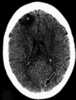

Dural sinus thrombosis

Cerebral venous sinus thrombosis (CVST) is the presence of a blood clot in the dural venous sinuses, which drain blood from the brain. Symptoms may include headache, abnormal vision, any of the symptoms of stroke such as weakness of the face and limbs on one side of the body, and seizures. [Source: Wikipedia ]